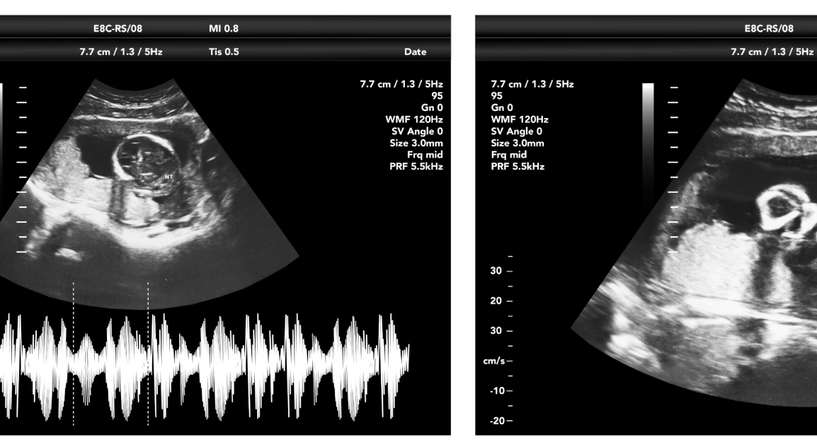

تُطمئن الدكتورة موريا توماسون، عالمة أعصاب الأطفال في كلية الطب بجامعة واين ستيت في ميشيغان في الولايات المُتّحدة الأميركيّة، أنّ إمكانيّة الوصول الى تشخيص الإصابة بالتوحّد داخل الرحم يلوح في الأفق. إذ يمكن أن يسهل استكشاف أدمغة الأجنة، باستخدام التصوير بالرنين المغناطيسي (MRI)، الكشف المبكر عن اضطرابات طيف التوحّد.

تستخدم تومسون وفريقها التصوير بالرنين المغناطيسي لفحص أدمغة الأجنة. ويُركّزون حاليًّا على “الحالات المحتملة للأطفال الذين وُلدوا قبل الأوان، والذين من المحتمل أن يكون لديهم المزيد من التأخر في النمو”. وغالبًا ما يُعزّى هذا التأخير إلى الإجهاد أو نقص الأكسجين أثناء الولادة.